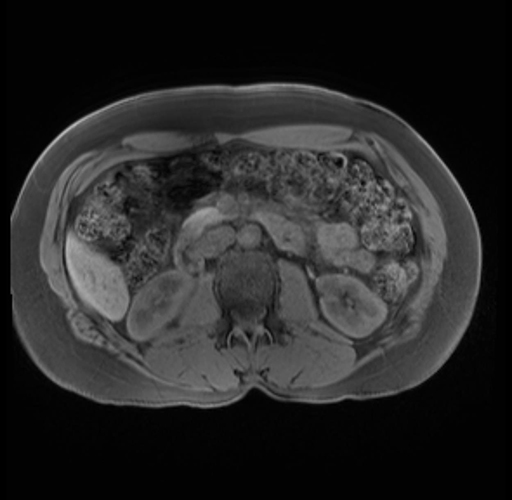

Imaging Analysis

Look through the patient's CT scan to identify any areas of concern for the necessary procedure.

Based on your CT findings, which issue(s) are present and would give reason for "planned slowing down moment(s)" in this case?